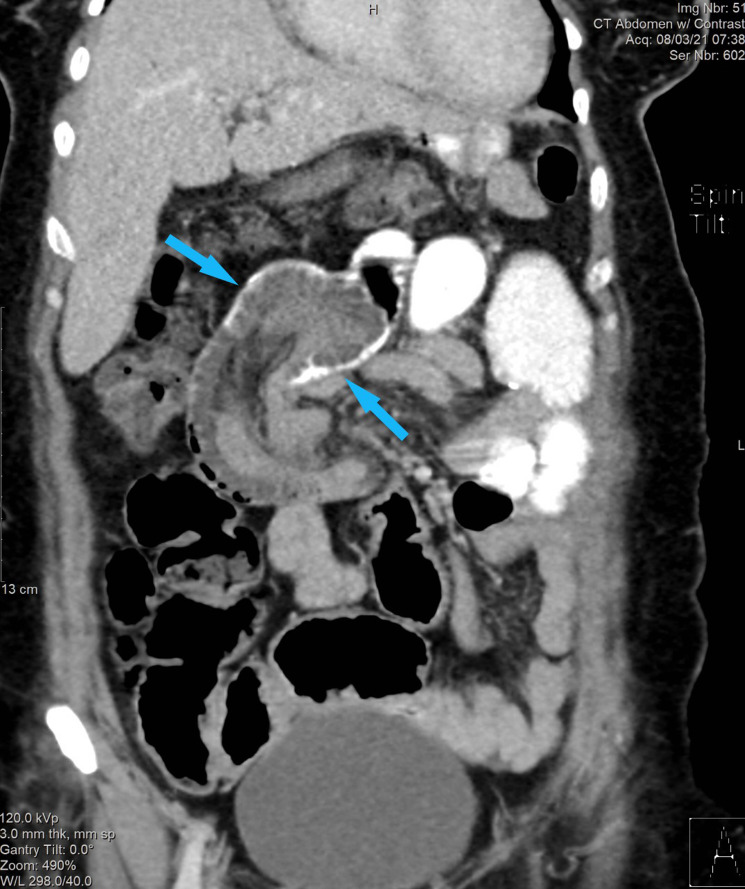

In figure 1, the intussusception can be seen in the CT coronal image of the abdomen and pelvis. This is demonstrated as a ‘bowel within bowel’ configuration with ingested contrast outlining the outer intussusceptum. Proximal small bowel obstruction is also seen.

The intussusception can be seen in the contrast-enhanced CT coronal image of the abdomen and pelvis. This demonstrates a ‘bowel within bowel’ configuration (blue arrow) with ingested contrast outlining the outer intussuscipiens. Proximal small bowel obstruction is also seen.